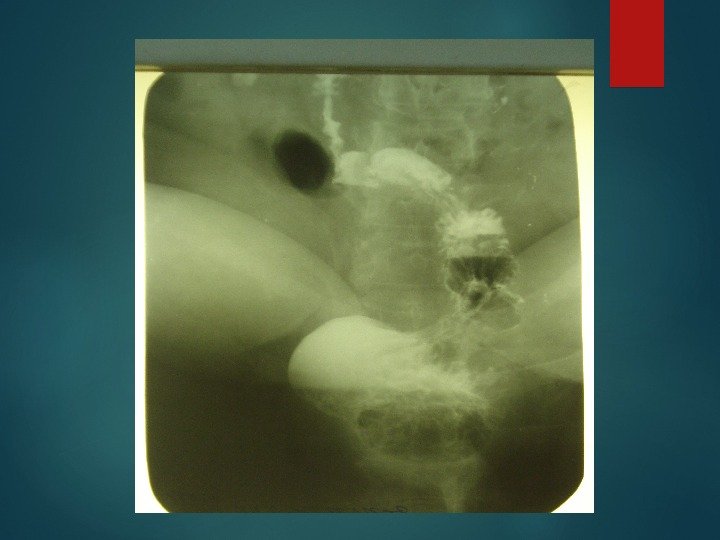

СКОЛЬЗЯЩАЯ ГРЫЖА ПИЩЕВОДНОГО ОТВЕРСТИЯ ДИАФРАГМЫ И ПЕПТИЧЕСКАЯ СТРИКТУРА НИЖНЕЙ ТРЕТИ ПИЩЕВОДА

Операц ия Ниссенаподшивание желудка к диафрагме вокруг пищеводного отверстия с фиксацией его малой кривизны к брюшной стенке для восстановления острого угла между дном желудка и брюшной частью пищевода; применяется для лечения рефлюксэзофагита и скользящей грыжи пищеводного отверстия диафрагмы

РЕНТГЕНОГРАФИЯ ЖЕЛУДКА ПОСЛЕ ФУНДОПЛИКАЦИИ ПО НИССЕНУ